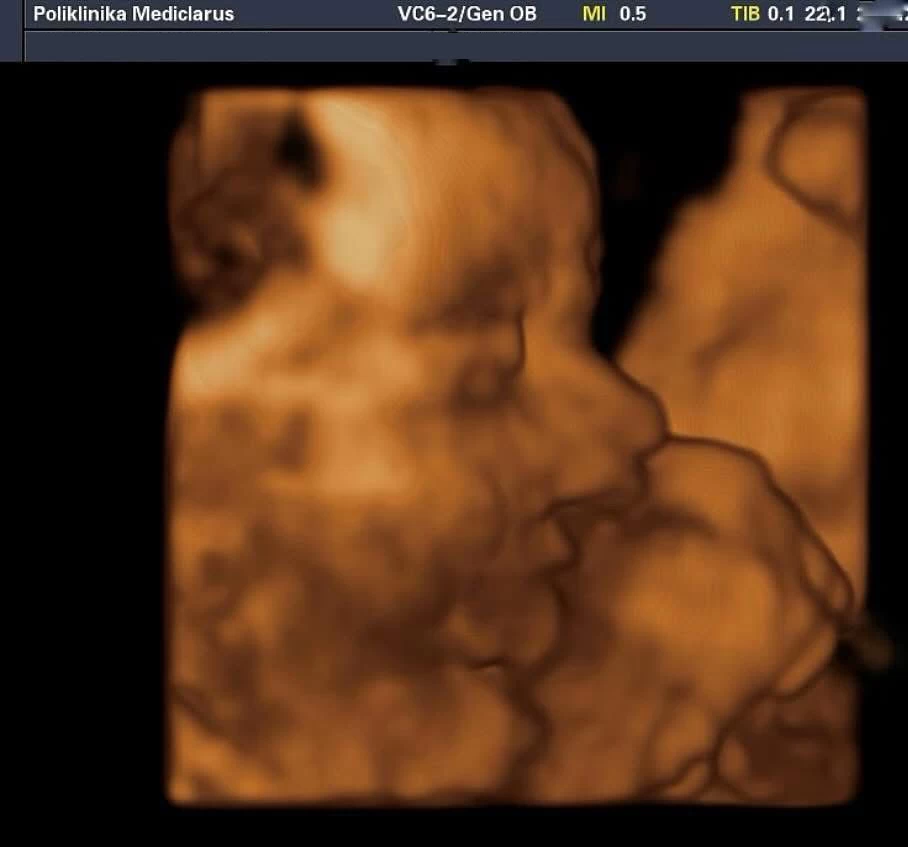

Zavirite u svijet svoje bebe uz najsuvremeniji 4D ultrazvuk

4D Ultrazvuk omogućuje realističan prikaz pokreta i crta lica vaše bebe!